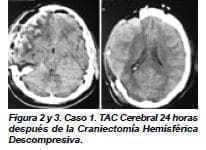

Se le practicó TAC cerebral (figura 1) en la cual se observó hematoma subdural agudo derecho con edema cerebral desviación de la línea media, contusiones corticales en región temporal derecha y fractura de la base de cráneo, en la roca izquierda, en el techo de la órbita derecha y en la silla turca.

La paciente fue llevada inmediatamente a cirugía y se le practicó craniectomía hemisférica derecha, drenaje de hematoma y se le practicó duroplastia de aumento, (dejando espacio) para que pudiera tolerar el edema cerebral. Se observaron múltiples áreas de contusión en corteza temporal y parietal, pero no se resecaron para preservar el tejido viable que pudieran contener. Se insertó catéter subdural para monitoria de la presión intracraneana (figuras 13).

En el postoperatorio inmediato, la paciente continuó sedada, con relajación muscular y en ventilación mecánica; se observó contracción de la pupila derecha y restauración del reflejo fotomotor. Presentó salida de líquido cefalorraquídeo por fosas nasales que perduró dos semanas; la presión intracraneana estuvo dentro de rangos normales y al cuarto día se retiró la monitoría.